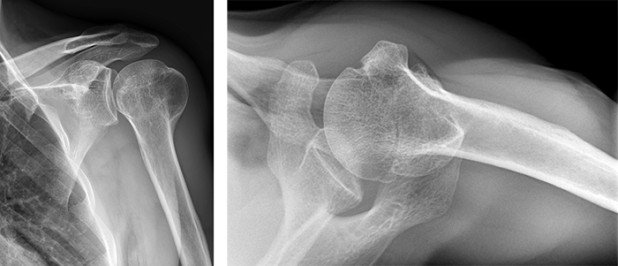

Auch bei der Kontrolle nach 3 Monaten konnten wir ein weiteres Fortschreiten der Knochenheilung im Röntgen dokumentieren. Klinisch bestand nun schon eine sehr gute Beweglichkeit bis über Kopf. Somit konnten wir die Freigabe zum kontrollierten Belastungsaufbau geben. Dabei sind jeweils allfällige Schmerzen als Marker für die Belastungsgrenze zu respektieren.

Nach 6 Monaten sahen wir den Patienten erneut zur Kontrolle. Das Röntgenbild zeigte einen verheilten Bruch. Die klinische Testung ergab einen nahezu wiederhergestellten seitengleichen Bewegungsumfang. Im Alltag bestanden fast keine Einschränkungen mehr, bis auf gewisse diskrete Beschwerden bei Belastungen. Die Physiotherapie wurde auf Grund der diskreten Resteinschränkung weiterverschrieben.

Nach 1,5 Jahren fand die abschliessende Kontrolle in unserer Sprechstunde statt. Der Patient war beschwerdefrei und hochzufrieden mit dem Heilungsverlauf. Er konnte all seinen sportlichen Freizeitaktivitäten wieder uneingeschränkt nachgehen. Der ehemalige Bruch war im Röntgen nicht mehr zu erkennen.